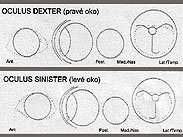

Konyaté Kemo Agent Arnak - eyes clean

Fata Morgana Agent Arnak - eyes clean

"Q" Pit-Pair Agent Arnak - eyes clean

Sparkling Centurion - eyes clean

- Naomi Gold Modrý dukát - eyes clean, DNA PRA +/+ DNA CEA +/- MDR1 +/+

- Tessa Gold Modrý dukát - eyes clean,DNA PRA +/+ DNA CEA +/- MDR1 +/+

- Vrhy sheltií: A+B+D+E+F+G+H+CH+I+J+K = DOV prostý

- Ája Agent Arnak - DOV prostý, PRA +/+ DNA CEA +/- DNA MDR1 +/-

- Andy, Archie a Así Agent Arnak - eyes clean, DOV prostý

- Así Agent Arnak - DNA CEA +/-, DNA MDR1 +/+

- Bee Maya Agent Arnak - DOV prostý, DNA CEA +/- DNA MDR1 +/+

- Bella My Dream Agent Arnak - DOV prostý, DNA PRA +/+ DNA CEA +/+ DNA MDR1 +/-